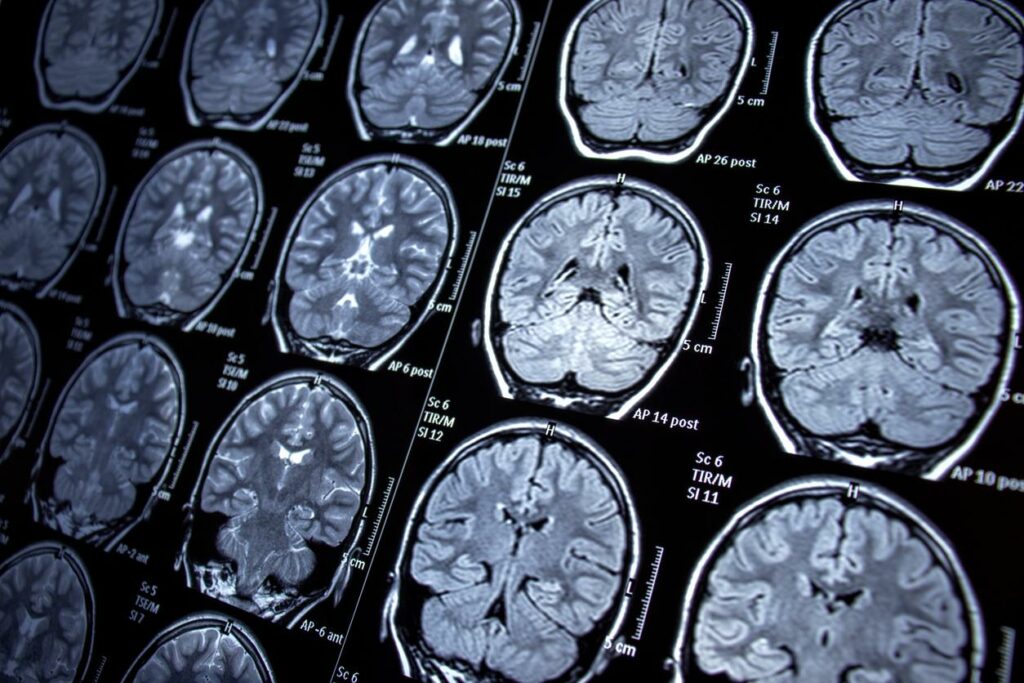

محققان در این پژوهش دادههای 8 هزار 766 شرکتکننده 65 ساله و بالاتر را بین سالهای 2016 و 2018 ارزیابی کردند؛ این دادهها شامل رژیم غذایی، اسکنهای MRI و ارزیابیهای شناختی بود. همچنین با پرسشنامه بسامد غذایی مصرف روزانه چای سبز و قهوه افراد اندازهگیری و در 4 سطح 0-200 میلیلیتر، 201-400 میلیلیتر، 401-600 میلیلیتر و بیشتر از 601 میلیلیتر طبقهبندی شد.

همچنین با اسکنهای MRI حجم ضایعات ماده سفید (WML)، حجم هیپوکامپ (HV) و حجم کل مغز (TBV) شرکتکنندگان محاسبه شد. محققان از مدلهای آماری پیشرفته برای تعدیل عوامل مختلف از جمله جمعیتشناسی، شرایط سلامتی، عادات سبک زندگی و عوامل خطر ژنتیکی برای بیماری آلزایمر استفاده کردند.

پس از تعدیل عوامل مختلف، محققان دریافتند که مصرف بیشتر چای سبز بهطور قابلتوجهی با حجم کمتر WML مرتبط بود. شرکتکنندگانی که روزانه 600 میلیلیتر چای سبز مصرف میکردند، حجم WML آنها 3 درصد کمتر از کسانی بود که 200 میلیلیتر یا کمتر مصرف میکردند؛ این رقم برای کسانی که روزانه 1500 میلیلیتر مصرف میکردند، 6 درصد بود. هیچ ارتباط معناداری نیز بین مصرف چای سبز و تغییر حجم هیپوکامپ یا کل مغز مشاهده نشد. مصرف قهوه نیز تأثیر قابلتوجهی بر حجم WML ،HV یا TBV نداشت.